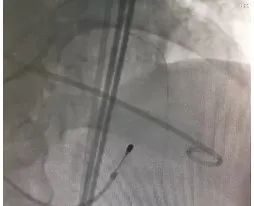

球囊扩张

瓣膜释放

• 22球囊于右无重叠角度扩张,植入24瓣膜;

• 剪内联鞘备snare,做chimney支架准备。